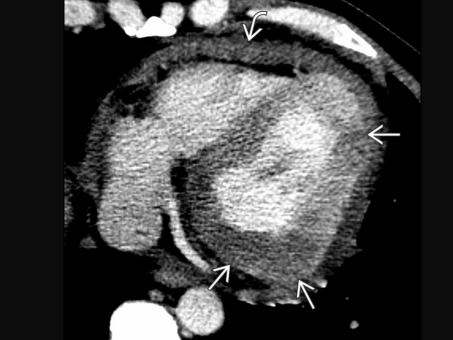

Metastases de mélanome VD et OD

Metastases de mélanome VD et OD